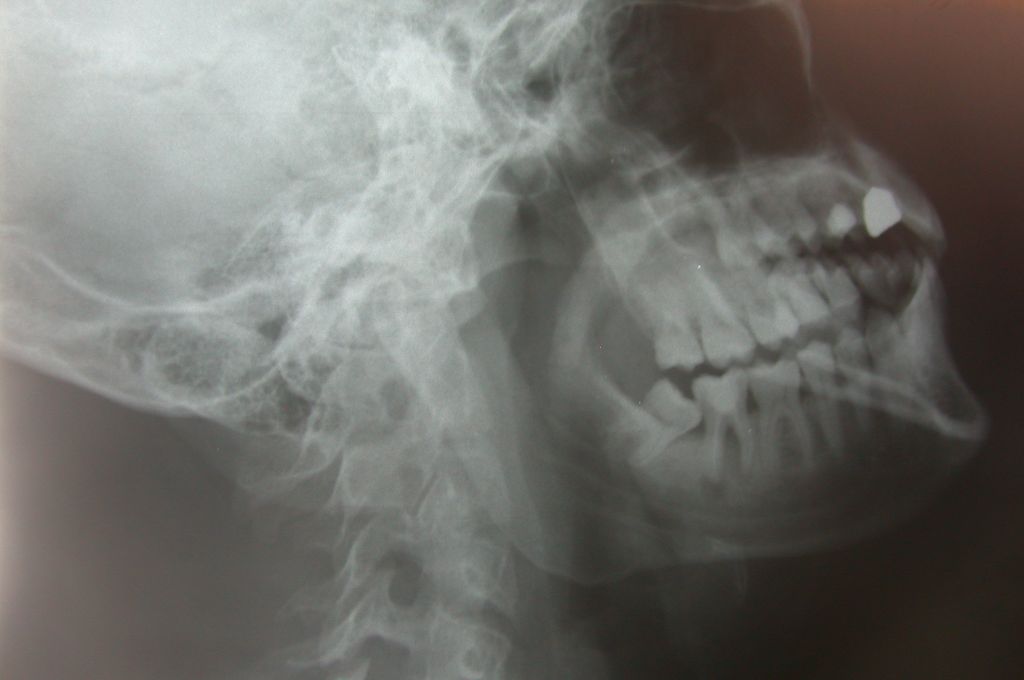

L’indagine radiodiagnostica normalmente prevista per questo tipo di intervento è l’ortopantomografia. Non essendo possibile effettuare tale esame presso la radiologia campale, gli Autori hanno sperimentato un’insolita proiezione laterale del cranio, denominata “radiografia laterale obliqua”, al fine di evidenziare l’eminandibola oggetto dell’intervento e ricavarne ugualmente le informazioni utili ai fini dell’avulsione chirurgica.

Materials and methods. Surgical interventions, including extraction of lower third molar, became necessary in the dental office. Since the equipment was not available, the Authors experimented an uncommon cranial projection called “oblique lateral radiography” to obtain a x-ray image of the lower jaw half. Conclusions. In this way it was possible for the surgeon to have all necessary information: anatomy and position of third molar and its relationship with lower alveolar nerve.